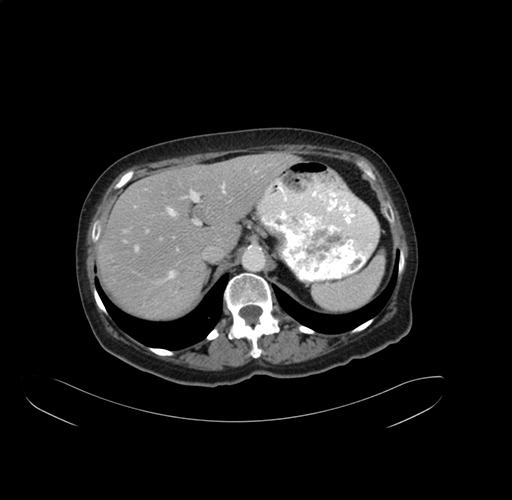

Axial Venous